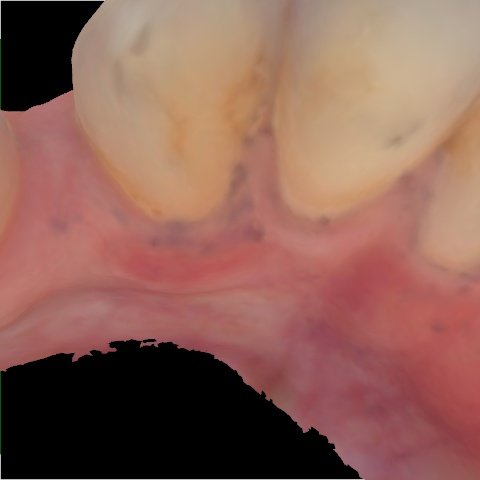

Image 63 / 400

NHD20738

Annotated as "Bad"

Original Image Rendering Image